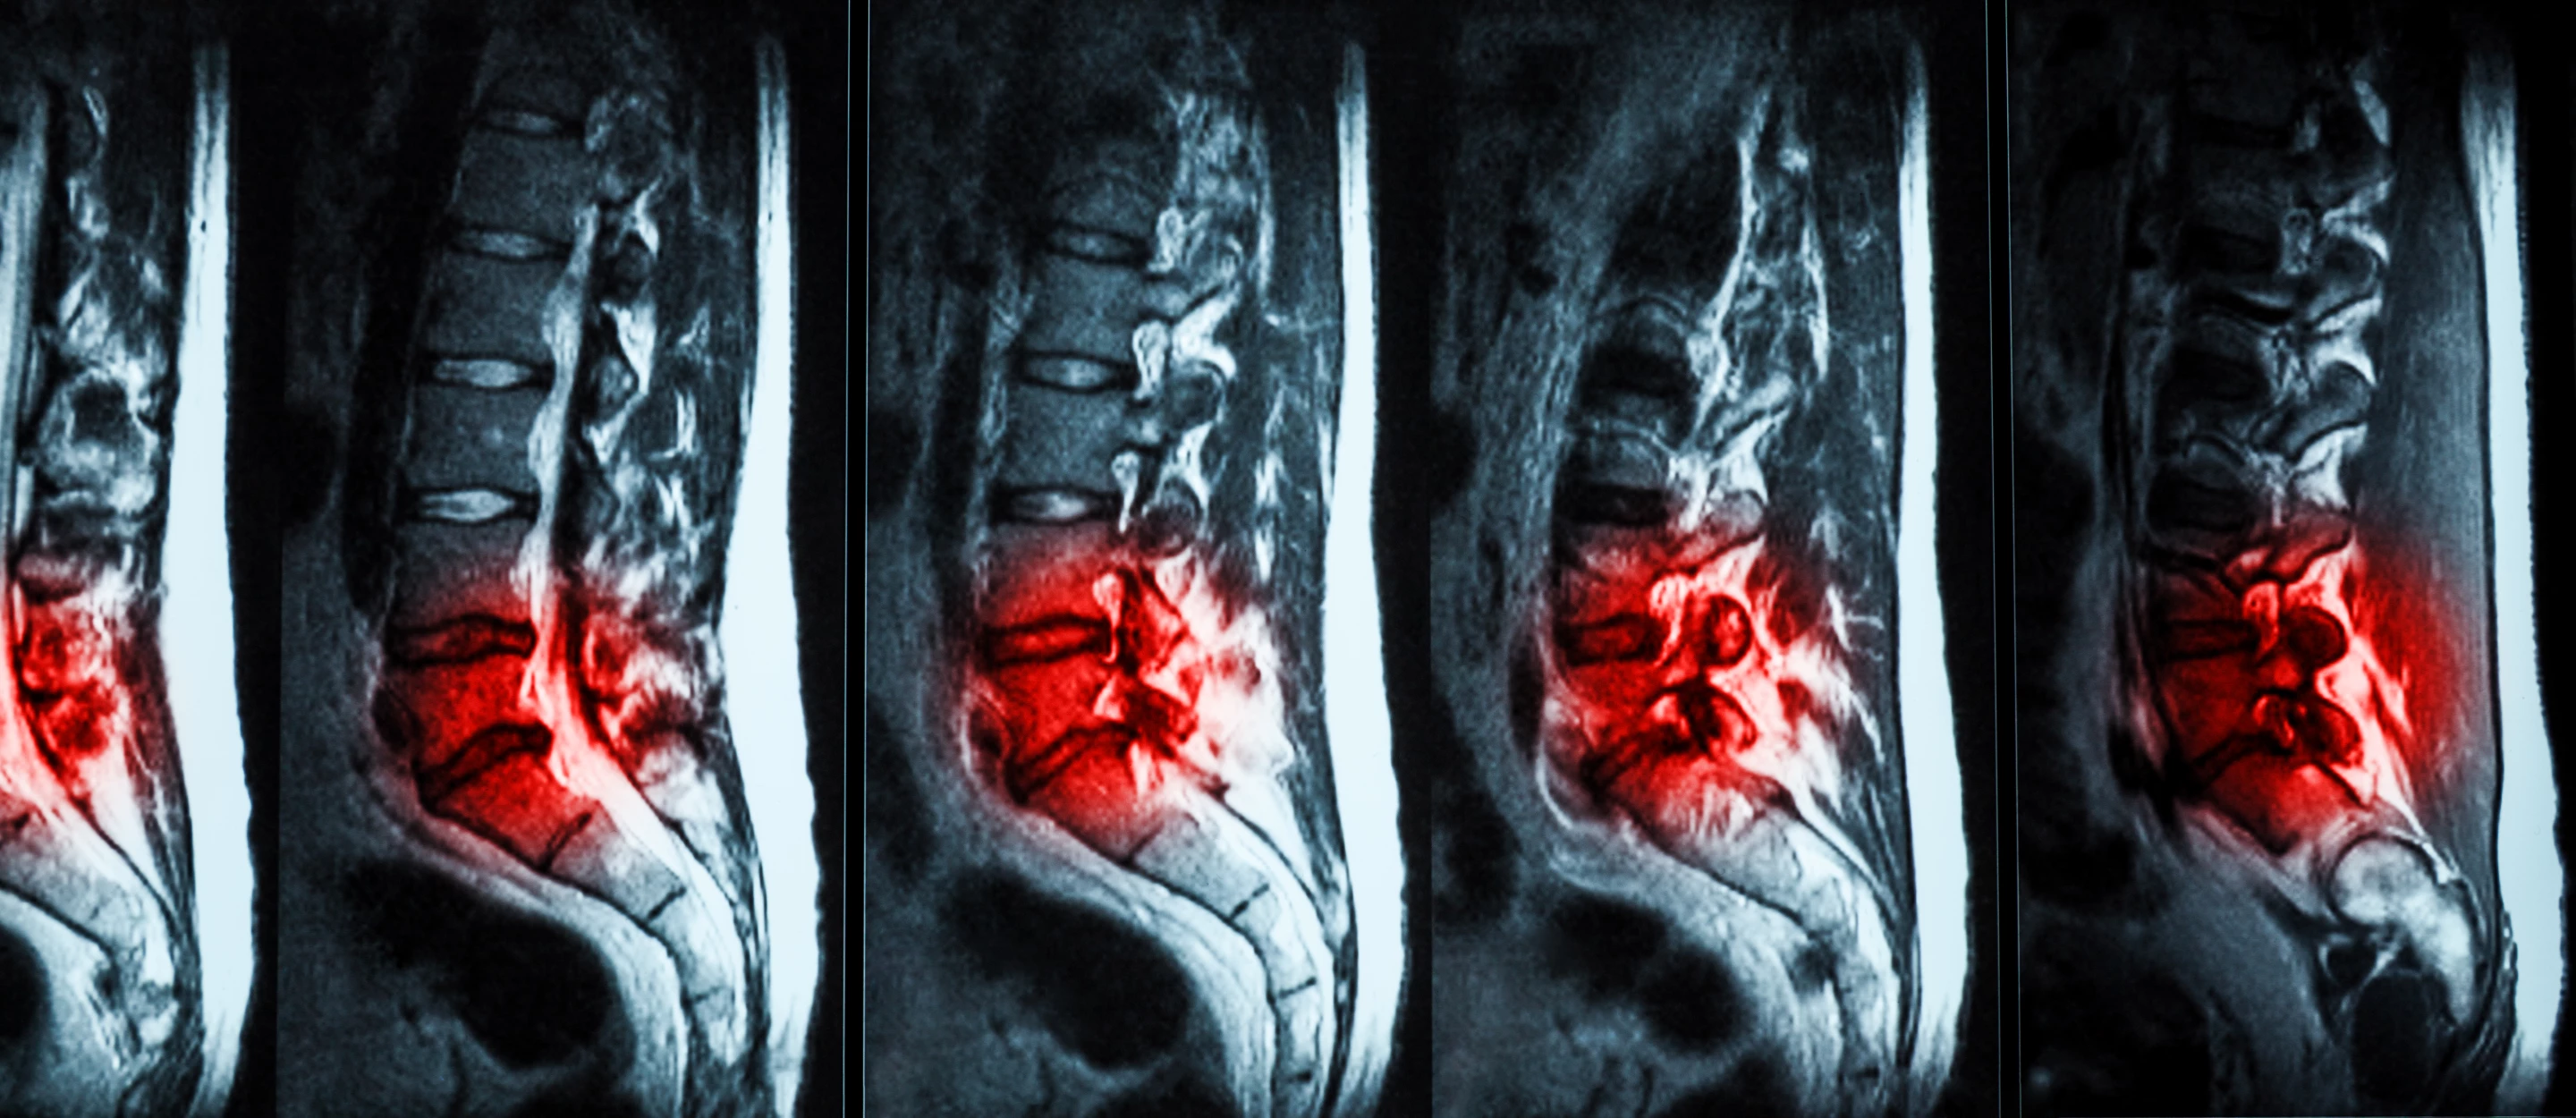

An injectable hydrogel has shown promise in repairing damaged spinal discs in a new human trial

Human trials have shown that hydrogel injections are a promising, effective treatment for chronic lower back pain caused by degenerative disc disease (DDD). The treatment is far less invasive than other surgeries, and has been given FDA approval.

Spinal discs play an important role in cushioning the vertebrae, but as with many parts of the body they begin to wear out with age. In many people, the fluid filling of the discs can dry up or leak out, causing pain and affecting mobility. Unfortunately, treatments are largely limited to care like rest, physical therapy and painkillers, or in more severe cases, surgery where discs are removed or replaced with prosthetics.

But recently, scientists have developed a new option – a hydrogel that can be injected into the spine where it fills in cracks and tears in the affected disc, restoring some of its cushioning to alleviate pain. Developed by the medical company ReGelTec, the gel is known as Hydrafil, and in 2020 it received a Breakthrough Device designation from the US FDA. And now the results of the first human trials are in.